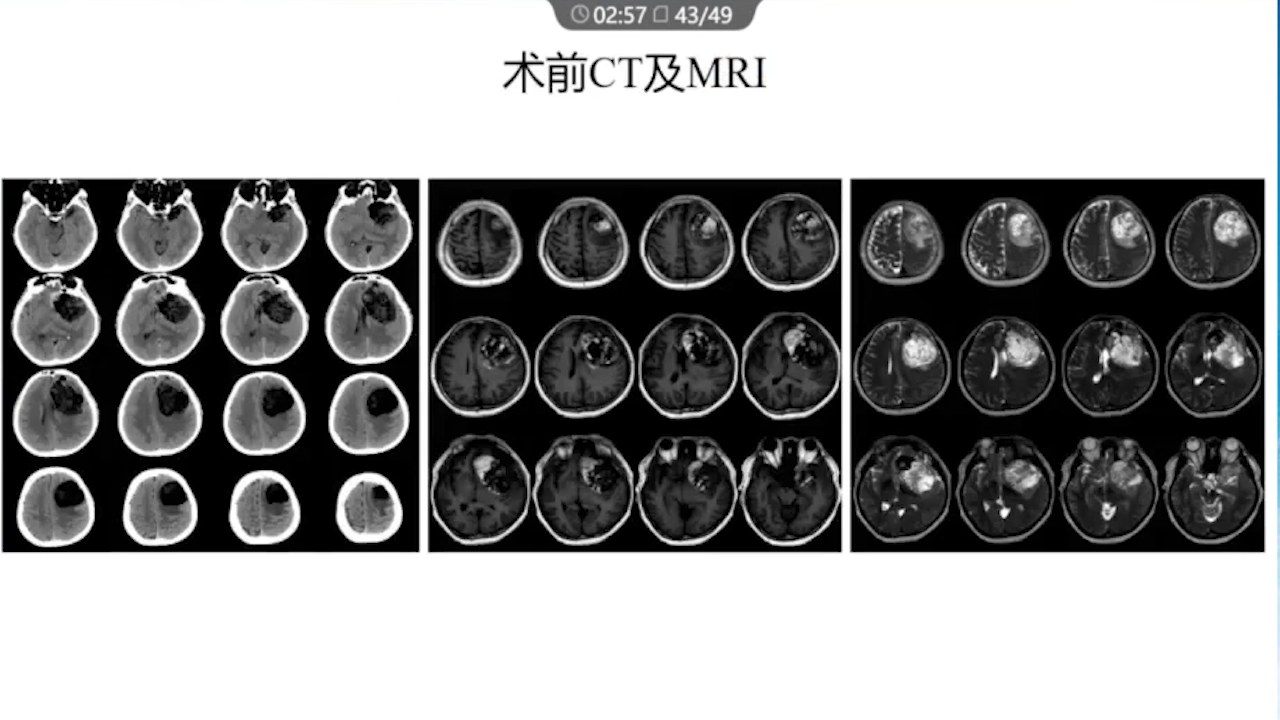

1、术前需要完善的影像学检查、多模态融合及神经导航以进行精确的肿瘤及静脉血管定位。